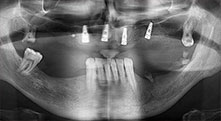

Professor Dr. Dr. Emanuel Bratu, maxillofacial surgeon, oral surgeon and prostheticist, is head of the implantology departments at two Romanian universities. He runs a renowned private hospital in Timisoara and is an internationally known researcher. In the interview Bratu explains why he considers that the W&H Piezomed piezosurgical device, and particularly two patented saws, have become essential for bone surgery.

Bratu: These saws feel completely different from previously available piezosurgical instruments. They are really astoundingly effective. We noticed immediately that the Piezomed B6/B7 work much faster than other saws. They are also easier to guide in bone, particularly in thick bone layers.

Bratu: Most dentists and oral surgeons have much more experience with rotary instruments. But piezosurgical instruments, with their special micro-oscillation, cut more precisely and are more controllable than rotary instruments. They are now at least as effective as rotary instruments. This is certainly the case for the Piezomed, at least. The bone loss is also less compared with rotary saws or milling cutters. Another very important factor is the improved overview: The coolant is set in motion by the ultrashort oscillations of the instruments. This causes a microcoagulation effect at the surgical site and thus reduces bleeding. The Piezomed also offers very bright illumination with the quadruple LED ring.

Bratu: We routinely use the instruments for harvesting bone blocks and splitting alveolar ridges. We also use the Piezomed B6/B7 for osteotomy of impacted teeth and removing failed implants. All indications that require deep, clean cuts.

Bratu: We prefer to harvest bone from the external oblique ridge of the posterior mandible, not from the interforaminal region. After the soft-tissue incision, we use the new saws to define the amount of bone to harvest. With this approach, we also use them for the entire preparation in almost 80% of cases. We may also use other piezo instruments and then at the end a chisel to mobilize the block. We find that this is a very effective surgical technique.

Bratu: We like to use the sandwich technique for augmentation in the lateral mandible. A bone cover is prepared with the piezo saw and the crestal fragment is fixed with microscrews. We place a mixture of autologous bone and xenogenic bone replacement material in between. This works very reliably. You should always ensure sufficiently dimensioned vertical cuts when splitting the alveolar ridge in the mandible. Otherwise the bone may fracture easily.